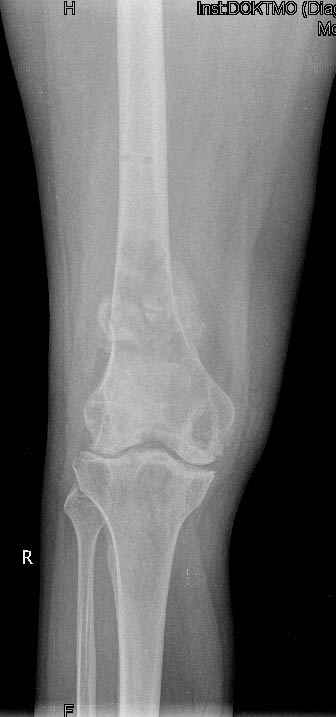

Коллеги!Окажите, пожалуйста, консультативную помощь.Мужчина, 41 год, 15 лет состоит на учете по поводу ревматоидного полиартрита, гормонзависимый (преднизолон получает нерегулярно). В процесс вовлечены крупные и мелкие суставы. 01.01.06 - без травмы наступил патологический перелом на границе н/3-с/3 бедра (перелом на фоне кистозных изменений?) Биопсия из зоны перелома - <реактивные изменения в очаге перелома>, без признаков опухоли. На рентгенограммах, помимо перелома, кистозные изменения на мыщелках б/берцовой кости и мыщелке бедра с другой стороны. До травмы со стороный коленных суставов был болевой синдром, функция практически в полном объеме. Какие будут предложения по тактика лечения перелома и кист на противоположом бедре? Заранее благодарю! С уважением, А.В.Владзимирский Донецкий НИИ травматологии и ортопедии Донецк, Украина